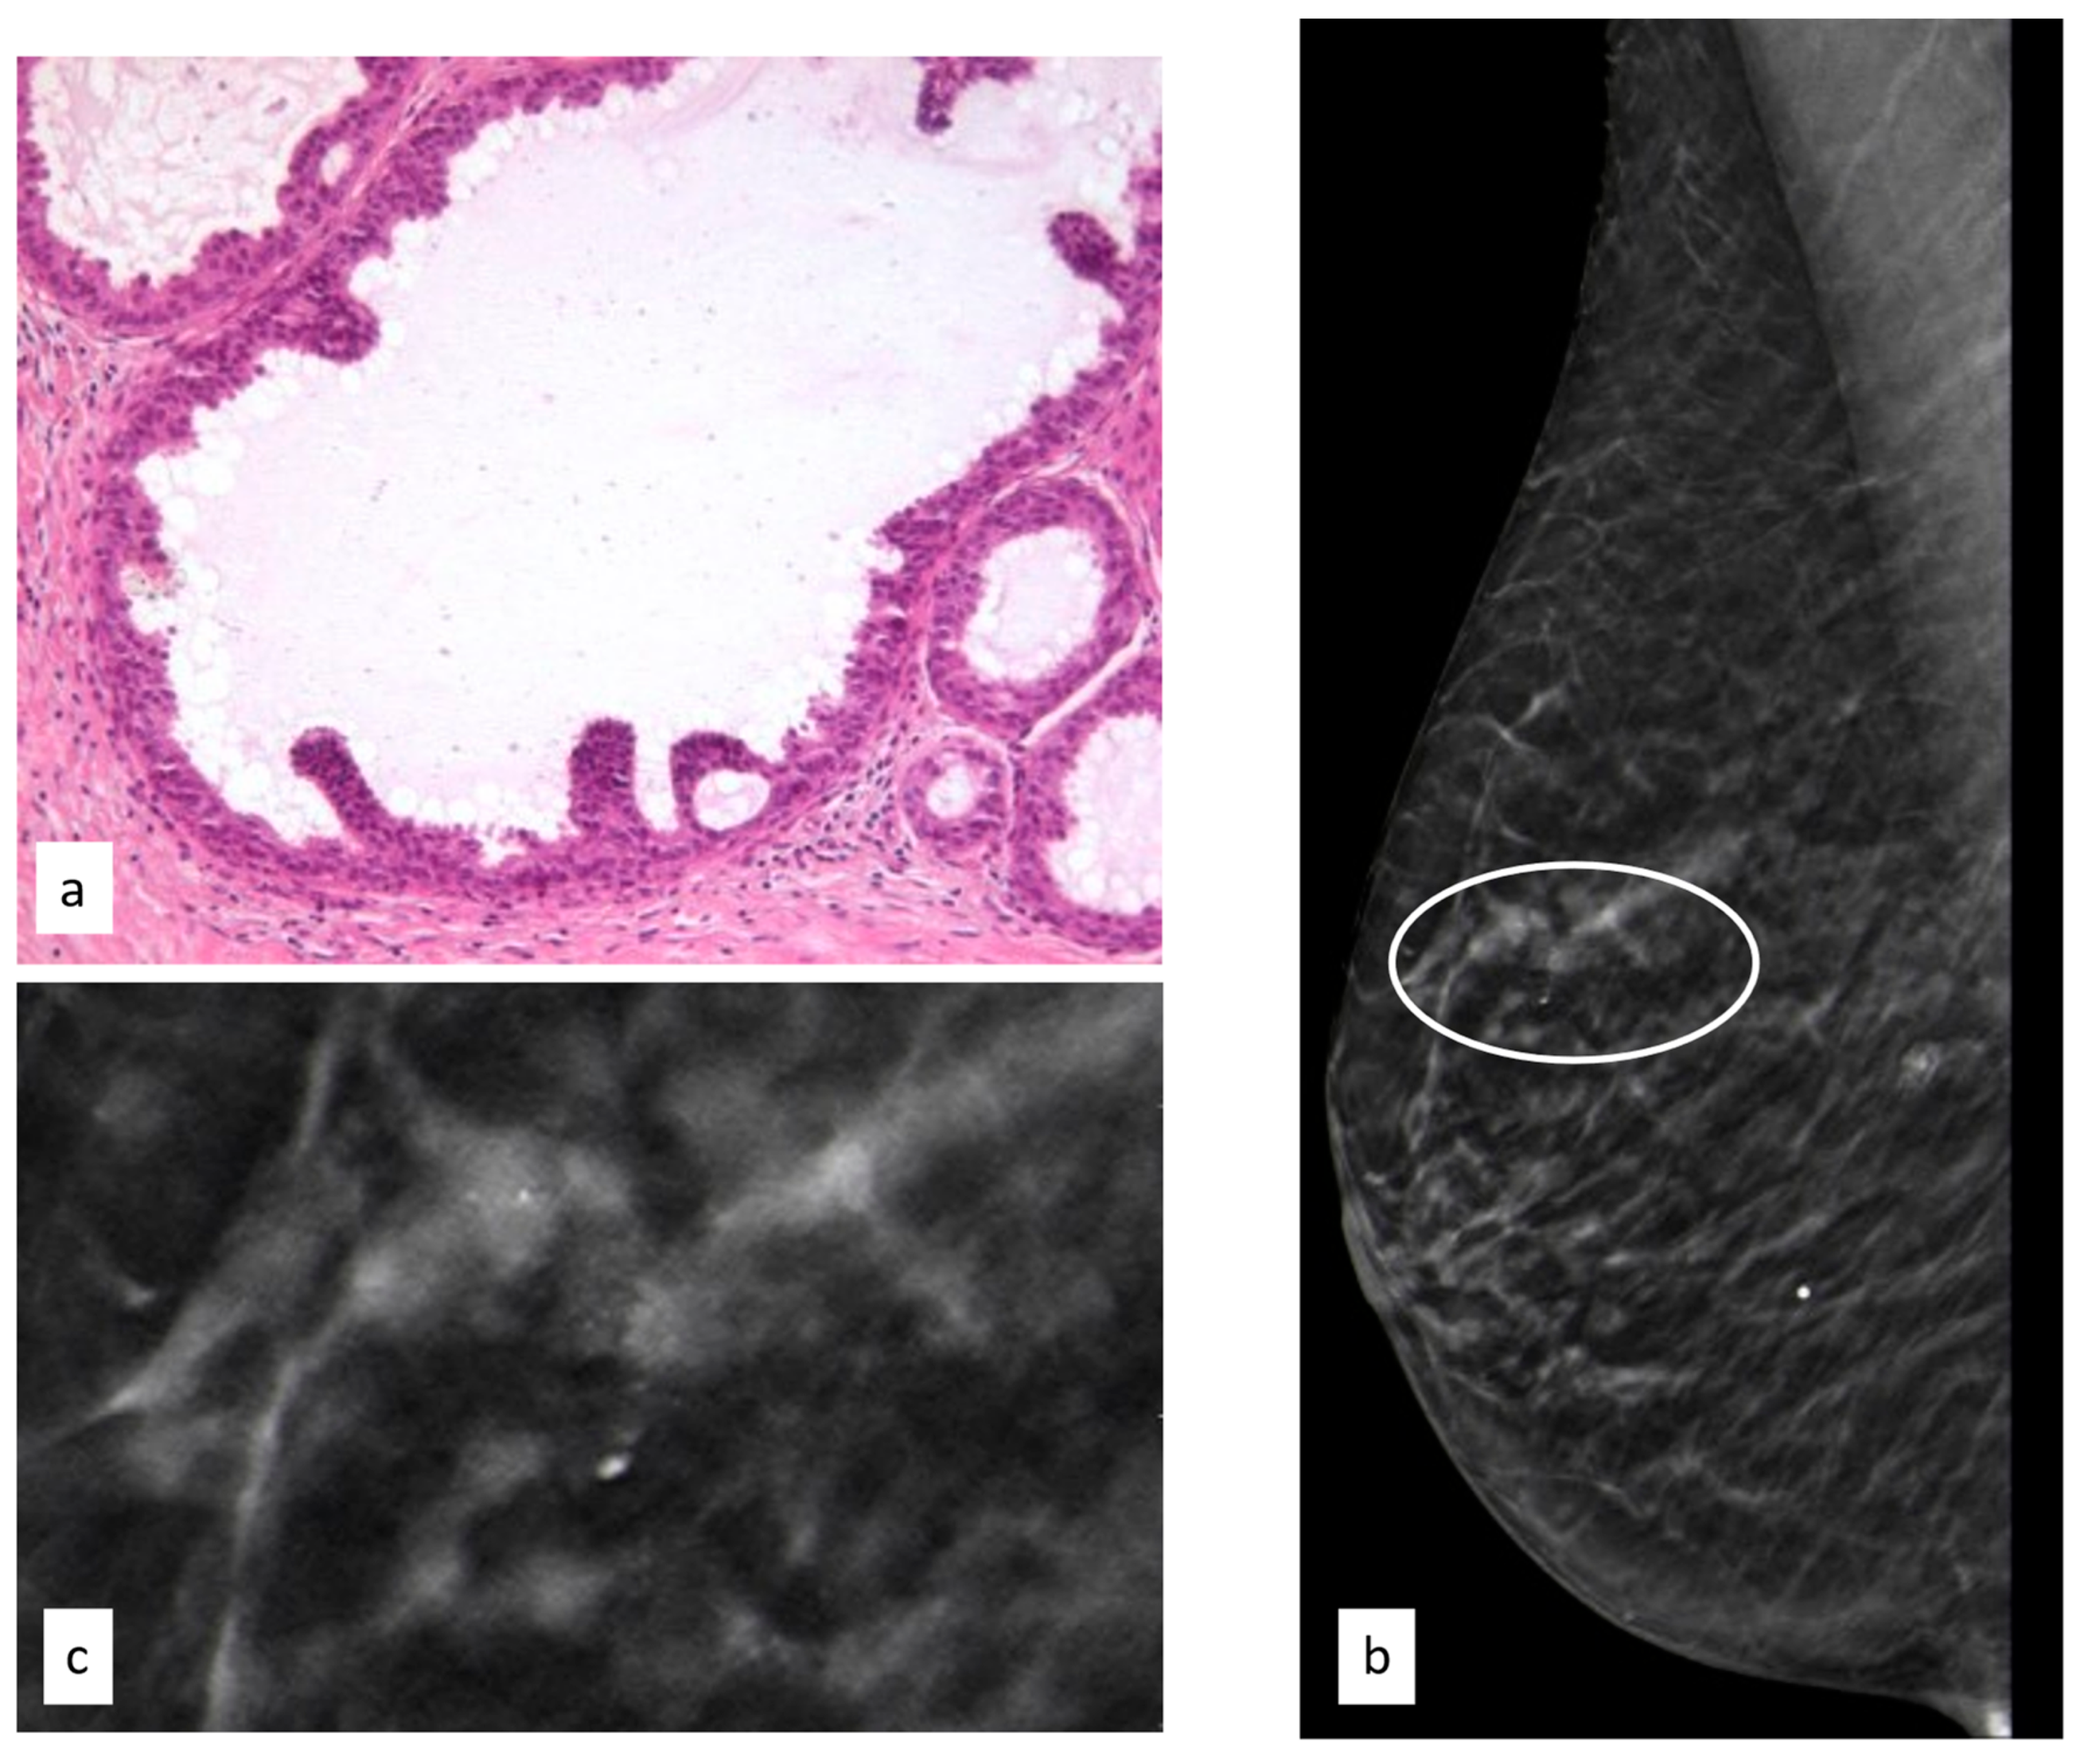

3.3.6. Radial Scar